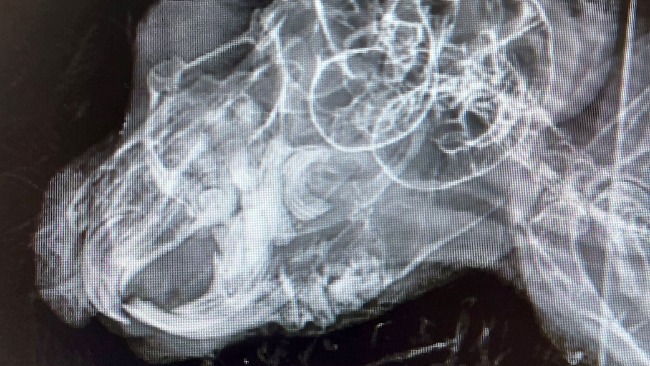

W badaniu stomatologicznym okazało się, że na dole po prawej stronie nie widać żadnego zęba! Dopiero na zdjęciu RTG okqzało się, że fragmenty zębów tkwią głeboko w zębodołach! Oprócz tego przerosty do środka jamy ustnej i przerosty wsteczne zębów.